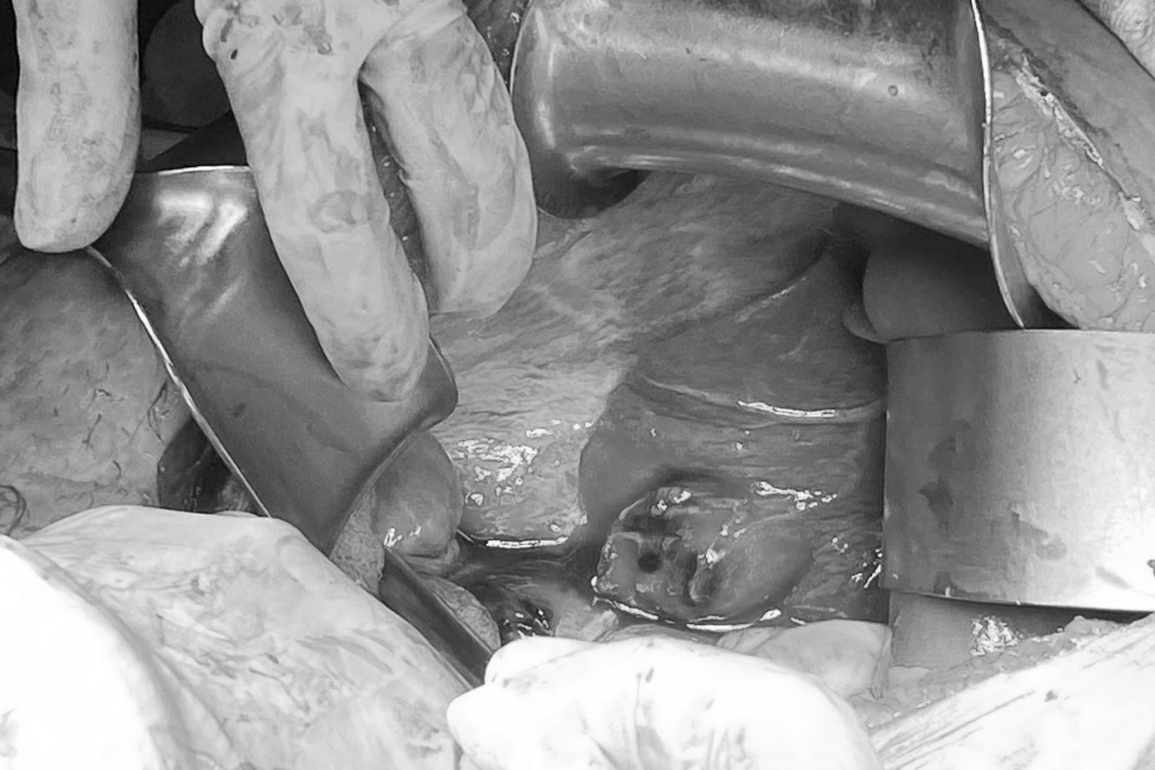

Ca phẫu thuật lấy thai trong góc gan diễn ra dưới sự phối hợp chặt chẽ của hai bệnh viện (Ảnh: Bệnh viện cung cấp).

8 giờ ngày 11/6 sau khi hội chẩn lần cuối, ê-kíp bác sĩ 2 bệnh viện quyết định sẽ mổ nội soi thám sát, đánh giá tình trạng khối thai trước, sau đó tùy tình trạng sẽ quyết định nội soi lấy khối thai hay chuyển sang mổ hở.

Quá trình tiếp cận vào bụng, bác sĩ thấy có 700ml máu loãng và 300ml máu cục vùng dưới gan, khối thai đóng ở phân thùy 6 của gan nằm sâu trong nhu mô gan đang chảy máu đỏ tươi. Ê-kíp điều trị rạch đường giữa trên rốn, tiến hành lấy trọn khối thai, đốt cầm máu nhu mô gan cẩn thận.